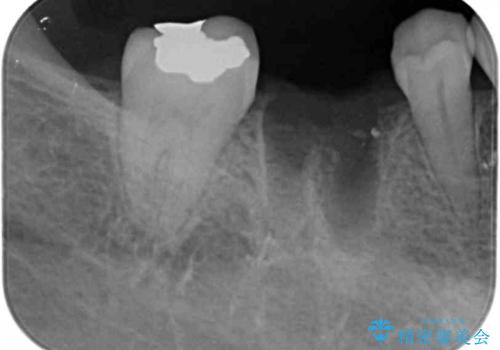

- 他院で虫歯治療に伴い初めての神経の治療を行ったところ、神経の治療自体10回以上通った上に抜歯と言われたとのことでした。

初診時には歯肉が腫れており、膿が出ている状態でした。

また、根の詰め物が根尖孔外(根の先の外の骨の部分)に盛大に漏れ出しており、歯周ポケットと根尖病巣が交通しているような状態でした。